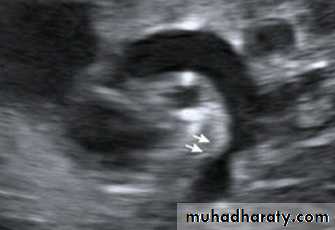

2-

Echocardiography shows the site and degree of coarctation, presence of left ventricular hypertrophy, and aortic valve morphology and function